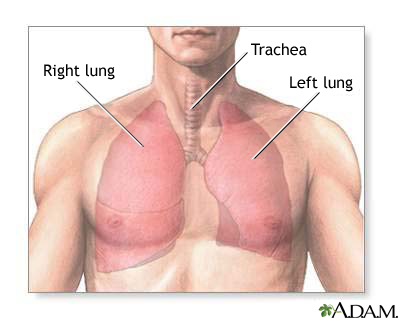

A chest CT (computed tomography) scan is an imaging method that uses x-rays to create cross-sectional pictures of the chest and upper abdomen.

A CT scan quickly creates detailed pictures of the body. The test may be used to get a better view of the structures inside the chest. A CT scan is one of the best ways of looking at soft tissues such as the heart and lungs.

- To determine the size, shape, and position of organs in the chest and upper abdomen